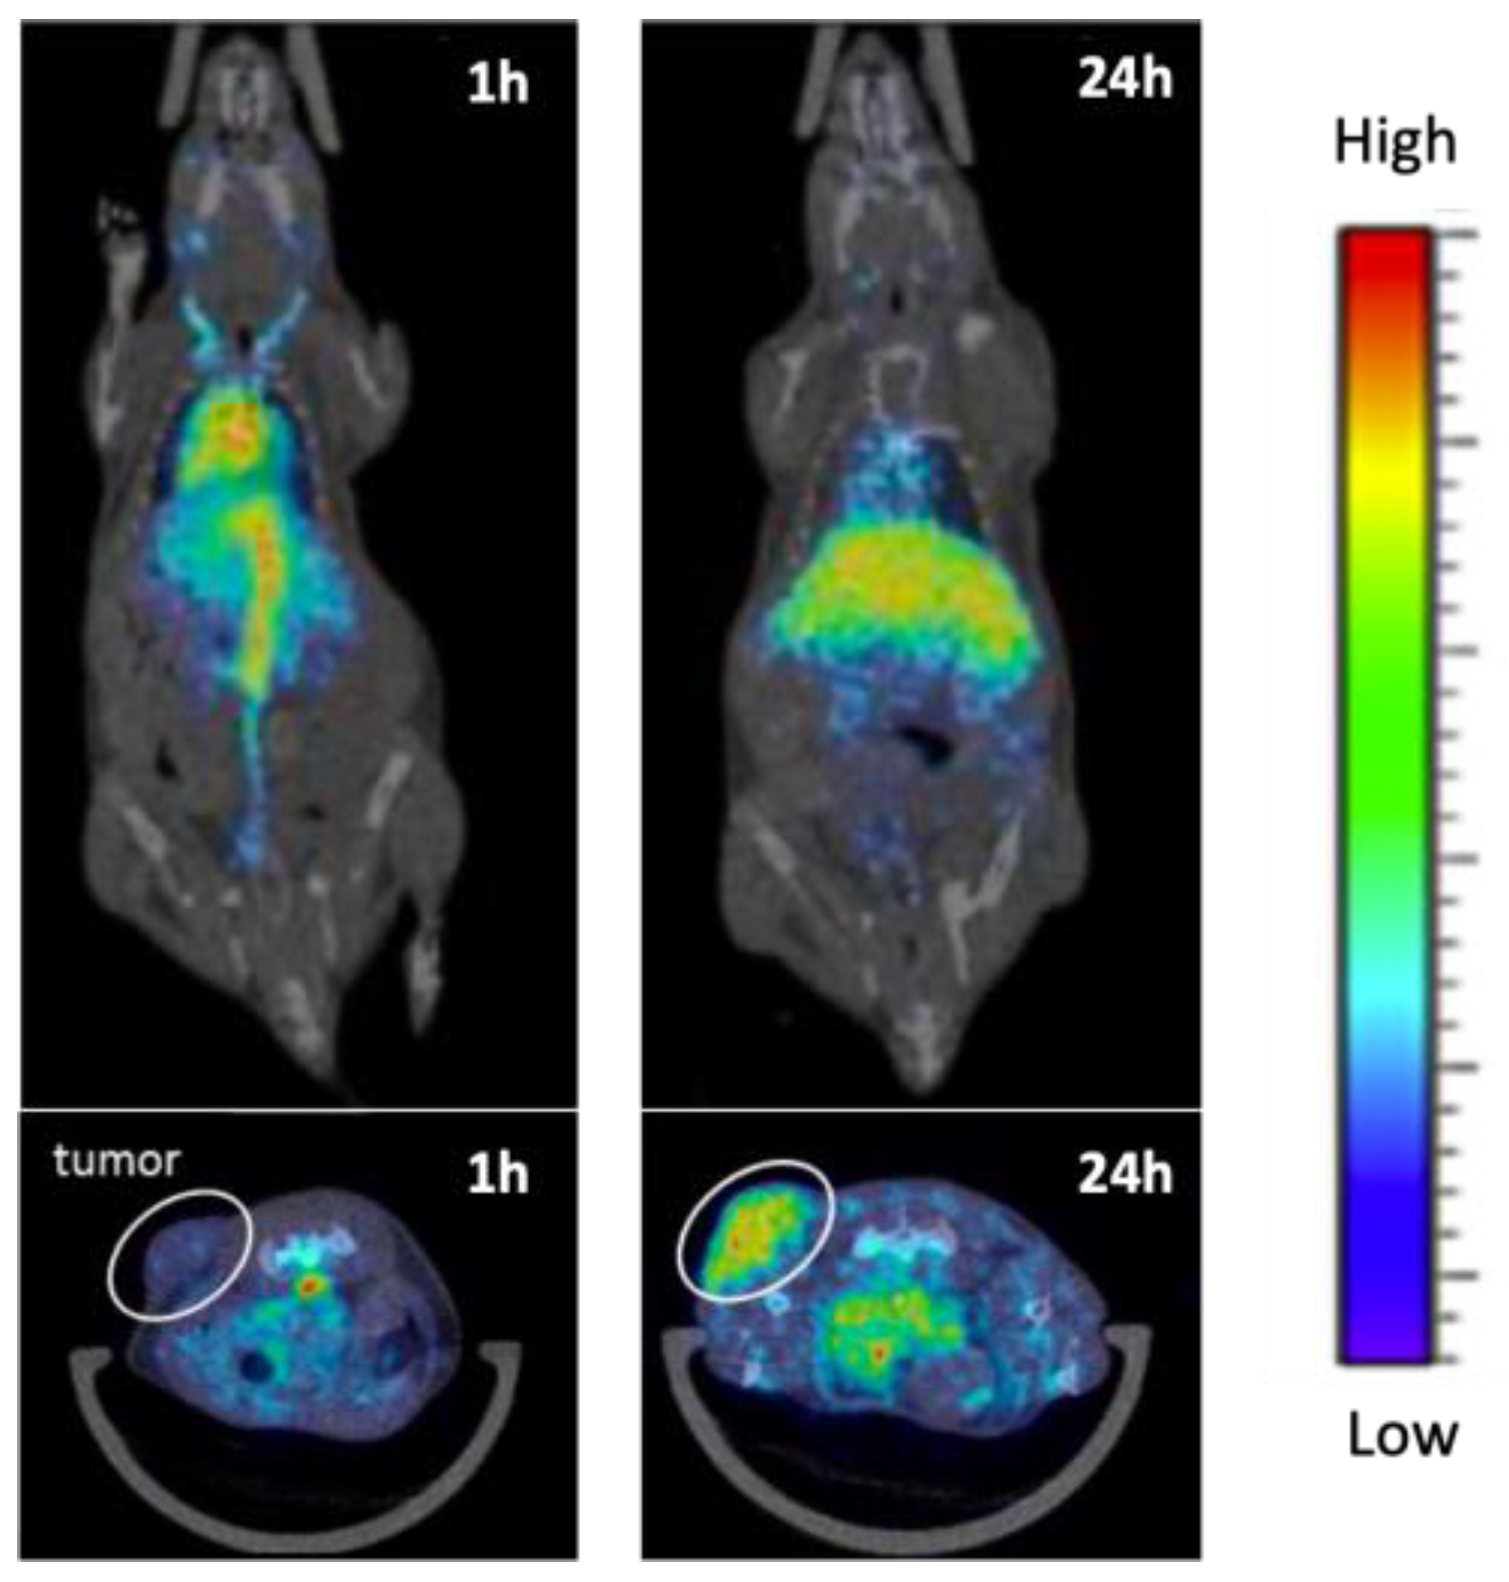

3.4. PET/SPECT